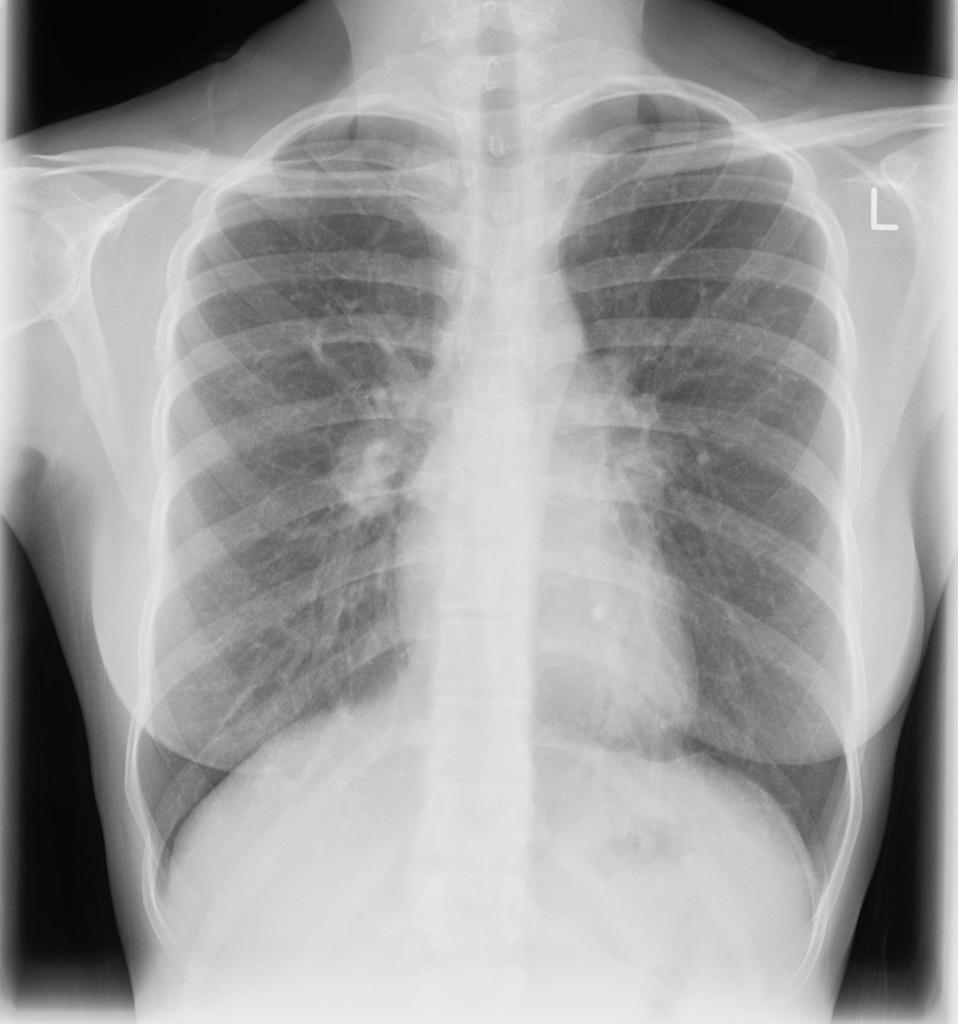

Example 2

Take a look at the following example showing consolidation. Click on the box to reveal the diagnosis.

Diagnosis

Right sided Pancoast Tumour